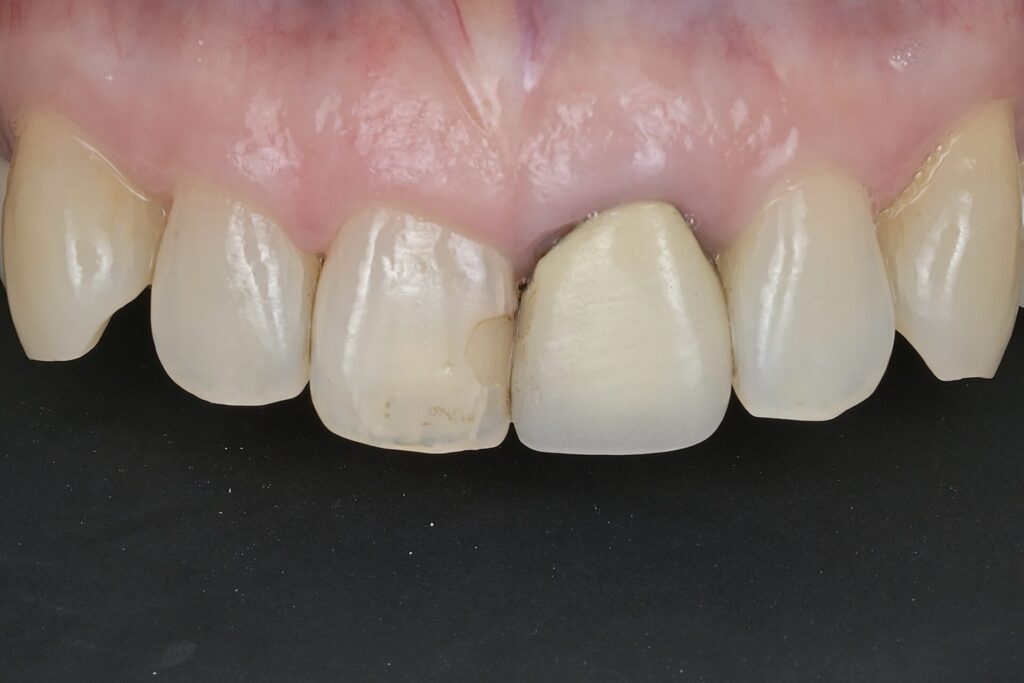

60代 審美治療 ジルコニアクラウン・虫歯治療 ダイレクトボンディング#55

Before

After

| 年齢 | 60代 | 治療方法 | ジルコニアクラウン/ダイレクトボンディング |

| 性別 | 女性 | 通院回数 | 6回 |

| 主訴 | 前歯を綺麗にしたい・歯を削る量を少なくしたい | 費用 | 308,000円(税込) |

| 治療のメリット | 歯を削る量を少なくできる・自然な見た目・境目がピッタリできる | ||

| 治療のデメリット | 大きい虫歯治療には適応できない場合がある | ||